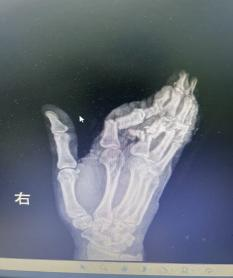

荊楚網(wǎng)(湖北日?qǐng)?bào)網(wǎng))訊(通訊員 嚴(yán)玉嬌 戰(zhàn)慧瑩)2026年3月1日16時(shí)09分,一陣急促的鳴笛聲在街道上響起,一輛轎車(chē)跨越1個(gè)多小時(shí)的路程從云夢(mèng)縣城飛馳而來(lái),緊急??吭诤焙教灬t(yī)院急診科門(mén)前。車(chē)上,34歲的余女士(化名)面色蒼白,她的右手被厚厚的紗布包裹,殷紅的血跡已滲透多層敷料——她的右手食指、中指、無(wú)名指三指完全離斷,小拇指嚴(yán)重?fù)p傷,無(wú)力地垂在一旁。

1小時(shí)前,余女士還在工作,一個(gè)不留神,粉碎機(jī)擠壓到了她的手,右手瞬間卷入機(jī)器。劇烈的疼痛襲來(lái),當(dāng)她抽出手時(shí),眼前的一幕讓她幾乎暈厥——食指、中指、無(wú)名指已完全離斷,只有少許皮膚還連著,小拇指也血肉模糊。

抵達(dá)醫(yī)院時(shí),航醫(yī)骨外科值班醫(yī)生已接到通知,在急診待命。接到余女士的那一刻,值班醫(yī)生迅速上前為她查看傷情“您別擔(dān)心,一切有我們”,經(jīng)快速檢查,診斷明確:余女士的右手多指完全離斷傷。這是一類(lèi)極為嚴(yán)重的手部創(chuàng)傷,斷指再植手術(shù)的黃金時(shí)間僅有6-8小時(shí),一旦治療時(shí)間稍有延誤,難以保證手指存活。